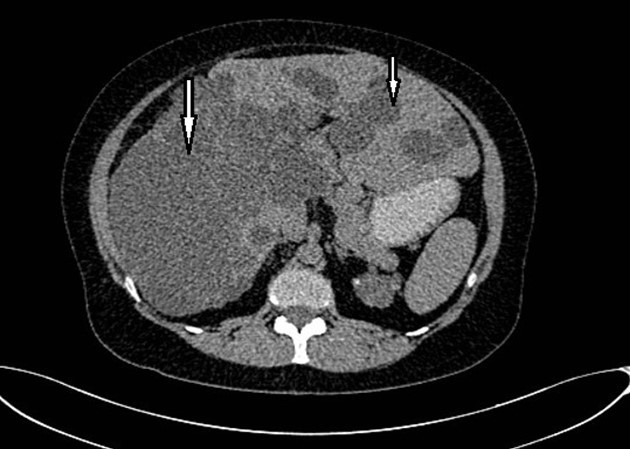

Abdominal tomography reported hepatomegaly secondary to polycystic disease and was reported with 3 cysts of greater size of 17, 14 and 12 cm in approximate diameter (Figure 1, Figure 2), kidney transplant without problems; the liver with mass effect on the stomach, the vena cava partially occluded, uncomplicated colon diverticulosis. Laboratory creatinine 1.44mg/dl urea 51.9 md/dl, glucose 71mg/dl, normal liver function tests.

Figure 2.Non-contrast CT shows multiple liver cysts with variable size and multiple renal cysts.